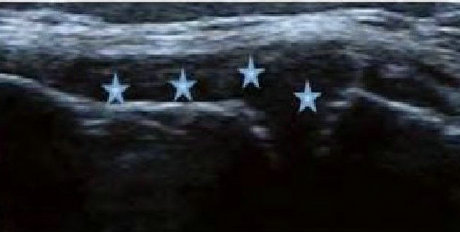

类风湿关节滑膜炎症会导致滑液渗出不断增多,形成关节腔积液。肌骨超声最少可发现1ml的积液,能对关节腔积液量及位置准确定位,通过检测判定关节腔内液性边界清楚的无回声区、细点状回声或细微的低回声条纹,判断其宽度和深度衡量积液量的多少,进而评估RA的严重程度。

Ⅰ级微量积液

滑膜囊内见前后径3.55mm液性暗区,呈椭圆形

Ⅱ级较多量积液

暗区内有团状高回声,可见深度达6.46mm液性暗区

Ⅲ级大量积液

关节囊扩张,可见大范围液性暗区,髌上囊积液深度达11.2mm